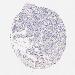

OVARIAN CANCER - Protein expressioni

A mouse-over function shows sample information and annotation data. Click on an image to view it in a full screen mode. Samples can be filtered based on level of antibody staining by selecting one or several of the following categories: high, medium, low and not detected. The assay and annotation is described here.

Note that samples used for immunohistochemistry by the Human Protein Atlas do not correspond to samples in the TCGA dataset.

Antibody stainingi

Antibody staining in the annotated cell types in the current human tissue is reported as not detected, low, medium, or high, based on conventional immunohistochemistry profiling in selected tissues. This score is based on the combination of the staining intensity and fraction of stained cells.

Each image is clickable and will lead to virtual microscopy that enables deeper exploration of all samples and also displays staining intensity scores, fraction scores and subcellular localization as well as patient and tissue information for each sample.

Antibody HPA003134

Antibody CAB002625

Staining

High

Medium

Low

Not detected

Intensity

Strong

Moderate

Weak

Negative

Quantity

>75%

75%-25%

<25%

None

Location

Nuclear

Cytoplasmic/membranous

Cytoplasmic/membranous,nuclear

Cystadenocarcinoma, mucinous, NOS

Carcinoma, endometroid

Cystadenocarcinoma, serous, NOS